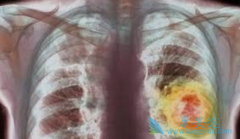

肺癌药物 易瑞沙 会导致患者出现严重且可能致命的副作用间质性肺炎,目前已有严重的间质性肺病病例的报道,包括致命病例和间质性肺炎或肺纤维化。对于有间质性肺炎或肺纤维化病史的患者在服用易瑞沙时一定要谨慎。一旦出现呼吸困难、咳嗽和发热等症状时 ...

我们知道 易瑞沙 的副作用里最严重的是间质性肺炎,因为有致命的危险,那么易瑞沙(吉非替尼)引起间质性肺炎的几率有多大呢?全球因易瑞沙(吉非替尼)所导致的间质性肺炎的平均发病率约1%,在我国的发病率更低,只有0.5%。至于由易瑞沙(吉非替尼)引 ...